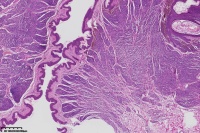

背部包块,皮内痣?

性别

女

年龄

41岁

背部包块

图4

考虑符合:皮内痣

皮内痣

皮肤皮内痣,切缘未净